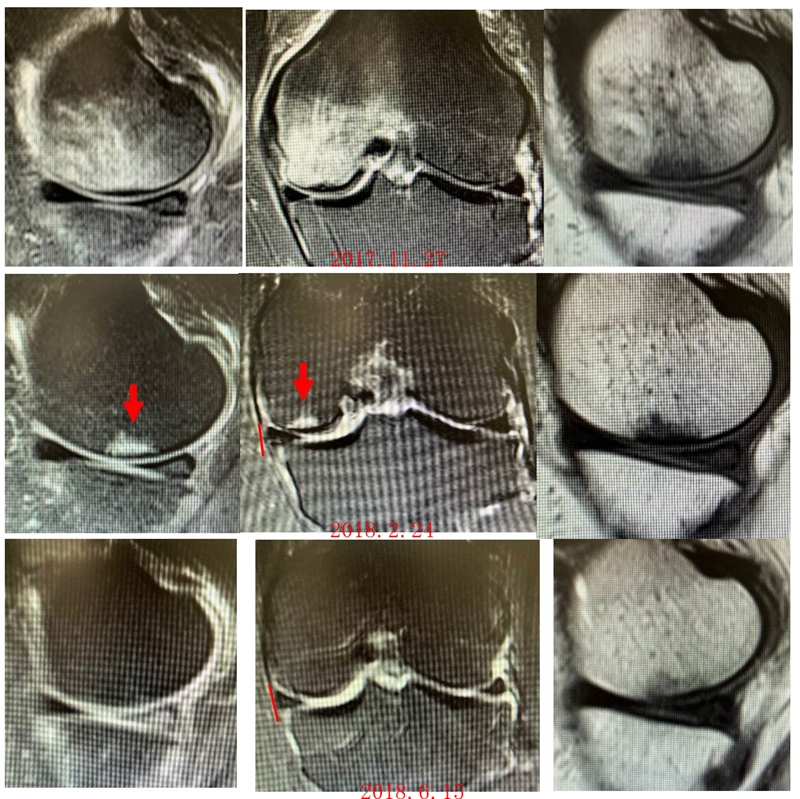

病例2:女,69岁,主诉左膝关节内侧疼痛1月余。2017年11月X光见右膝股骨髁负重区的软骨下区域出现了椭圆形透亮影,MR检查见股骨内侧髁骨坏死,合并内侧半月板外突和后角层裂,半月板相对突出百分比(RPE)25.32%,矢状位病变区域前后径为23.96mm,关节线会聚角6°。

予克氏针钻减压,消炎止痛药物口服、静滴唑来膦酸钠注射液,避免负重6周,后改部分负重至3个月,患者依从性差。2018年1月复查MR见骨髓水肿少许吸收,坏死区扩大,半月板相对突出百分比(RPE)33.53%,矢状位病变区域前后径为26.89mm,患者仍有膝关节疼痛症状,建议行手术治疗,患者拒绝手术后失访。